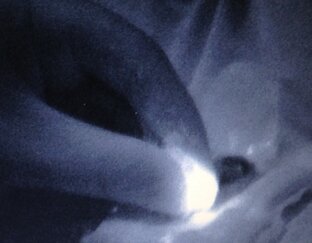

Биопсия сигнального лимфатического узла с фотографиями.